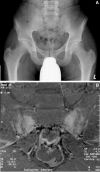

Ankylosing spondylitis (AS) is a complex, potentially debilitating disease that is insidious in onset, progressing to radiological sacroiliitis over several years. Patients with symptomatic AS lose productivity owing to work disability and unemployment, have a substantial use of healthcare resources, and reduced quality of life. The pathogenesis of AS is poorly understood. However, immune mediated mechanisms involving human leucocyte antigen (HLA)-B27, inflammatory cellular infiltrates, cytokines (for example, tumour necrosis factor alpha and interleukin 10), and genetic and environmental factors are thought to have key roles. The detection of sacroiliitis by radiography, magnetic resonance imaging, or computed tomography in the presence of clinical manifestations is diagnostic for AS, although the presence of inflammatory back pain plus at least two other typical features of spondyloarthropathy (for example, enthesitis and uveitis) is highly predictive of early AS. Non-steroidal anti-inflammatory drugs (NSAIDs) effectively relieve inflammatory symptoms and are presently first line drug treatment. However, NSAID treatment has only a symptomatic effect and probably does not alter the disease course. For symptoms refractory to NSAIDs, second line treatments, including corticosteroids and various disease modifying antirheumatic drugs, are employed but are of limited benefit. Emerging biological therapies target the inflammatory processes underlying AS, and thus, may favourably alter the disease process, in addition to providing symptom relief.